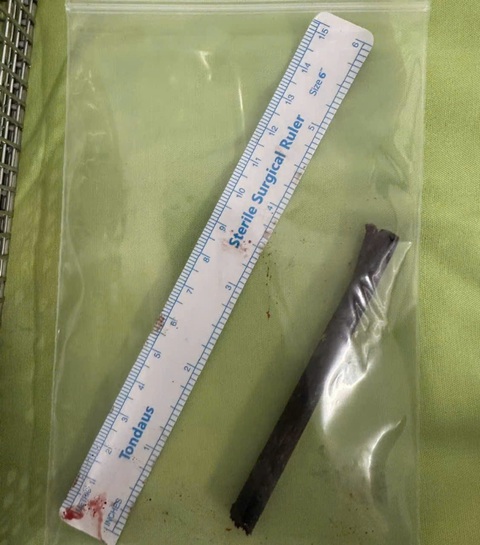

Ca phẫu thuật kéo dài gần 2 giờ, ê kíp lấy thành công dị vật là đoạn đũa dài 9cm, chiếc đũa xuyên thấu từ ngoài vào phá vỡ sàng ổ mắt, phá vỡ vách xoang hàm và ghim vào sàng mũi; đồng thời còn có các mảnh vụn xương và mảnh vụn của dị vật.

Dị vật một phần chiếc đũa được lấy ra khỏi sàng mũi bệnh nhân - Ảnh: BV